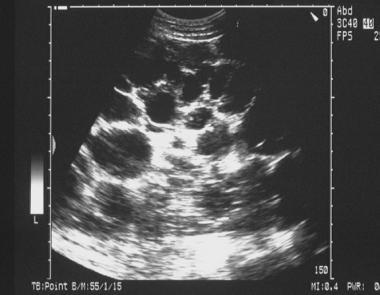

What’s that?

Cystic kidney disease

Polycystic kidney disease - kidney is filled with cysts/ above the centile that is expected for a child at given age